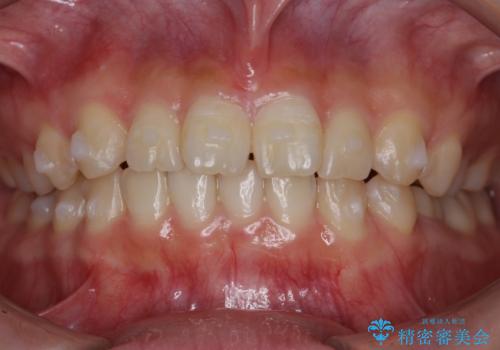

前歯のねじれ 乳歯を残して矯正治療

- 前歯のねじれを気にして来院。

左下に乳歯が残っていましたが、被せ物に穴が空いている状態でした。

乳歯は抜かずに保存的な治療を行いました。

上下の正中が1本分ずれていましたが、ちょうど1本分で目立たず、また、右下の歯が生まれつき少ないことを利用して、最小限の歯の移動にとどめました。